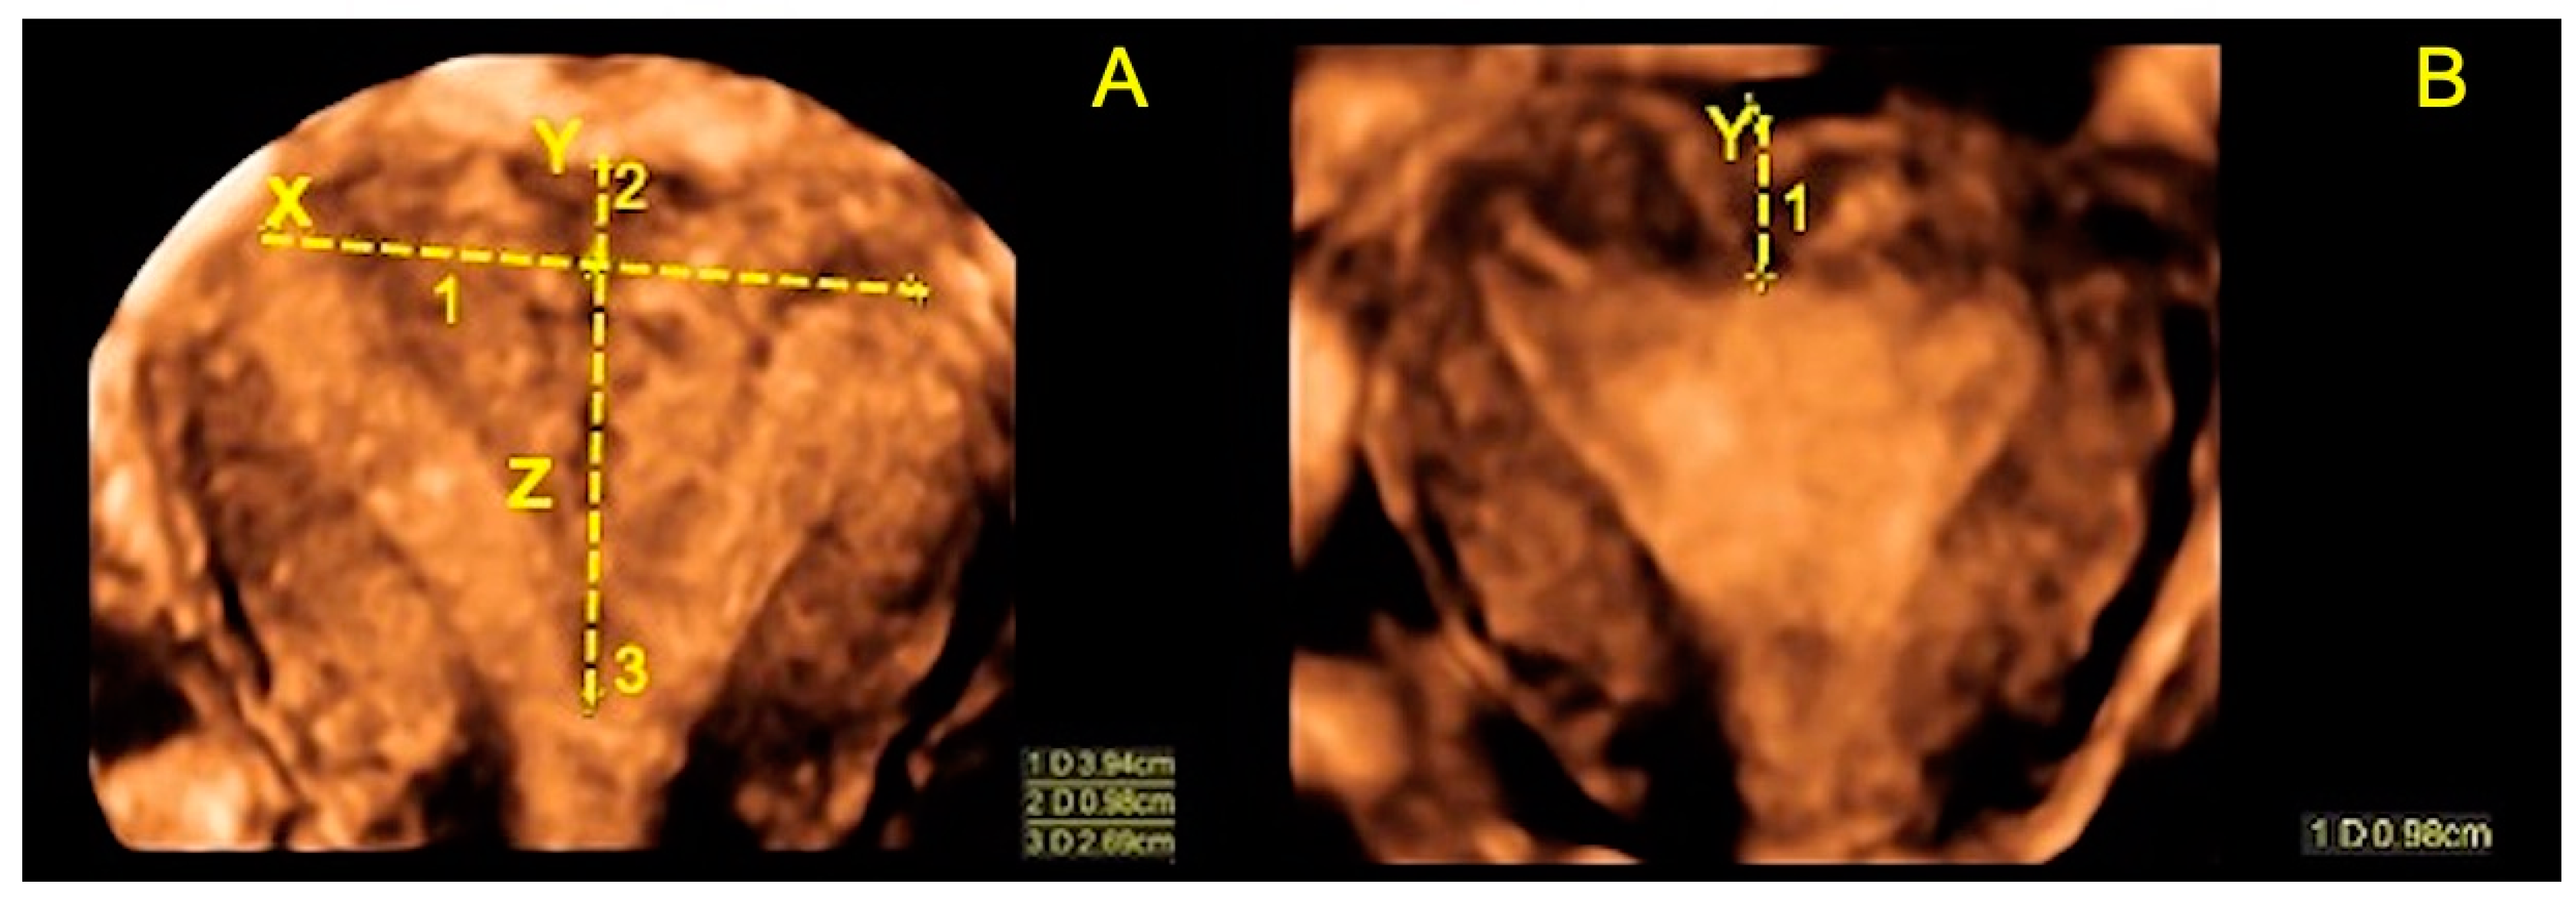

| Length of the septum, Z (mm ± SD) | 24.9 ± 5.13 |

| Thickness of uterine myometrial fundus, X (mm ± SD) | 5.9 ± 1.94 |